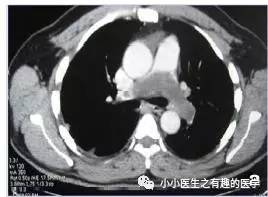

看CT,左肺动脉血栓了。

病人结局呢?

遗体解剖发现肺动脉肿块,延伸至右心房。病理:原发性肺动脉绒毛膜癌。At autopsy, a tumour was found occluding the left pulmonary artery extending into the right atrium.Histological evaluation showed a primary choriocarcinoma。

这不是癌栓,这是肺动脉的肿瘤。